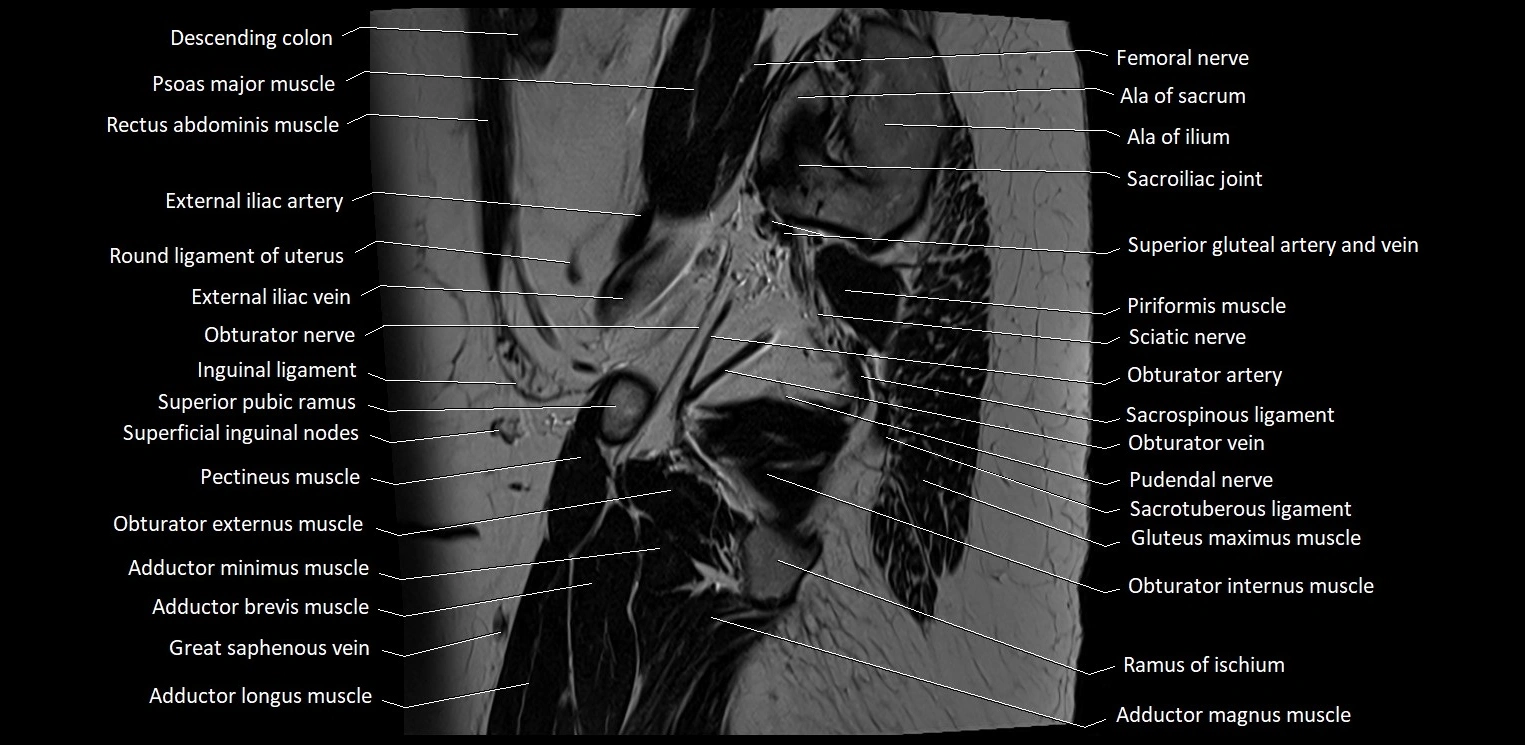

- Adductor brevis muscle

- Adductor longus muscle

- Adductor magnus muscle

- Adductor minimus muscle

- Ala of ilium (wing of ilium)

- Ala of sacrum

- External iliac artery

- External iliac vein

- Femoral nerve

- Gluteus maximus muscle

- Inguinal ligament

- Lumbosacral trunk

- Obturator externus muscle

- Obturator internus muscle

- Obturator nerve

- Obturator vein

- Pectineus muscle

- Piriformis muscle

- Pudendal nerve

- Ramus of ischium

- Round ligament of uterus

- Sacral plexus

- Sacroiliac joint

- Sacrospinous ligament

- Sacrotuberous ligament

- Sciatic nerve

- Superficial inguinal lymph nodes

- Superior gluteal artery

- Superior pubic ramus